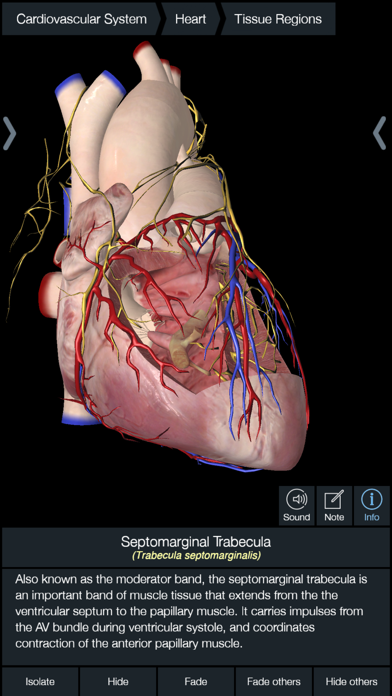

Downloading Essential Anatomy 5 IPA for iOS is a convenient and useful way to explore the world of human anatomy right from the comfort of your iPhone or iPad. This app provides a comprehensive and detailed view of the human body, allowing users to interact with various systems and structures. With stunning 3D graphics, it offers a visually captivating experience that aids in understanding and learning about the complexities of the human body. Whether you are a medical student, healthcare professional, or someone with a general interest in anatomy, Essential Anatomy 5 IPA is a must-have app that provides a wealth of knowledge at your fingertips. The app’s intuitive interface and easy navigation make it accessible to users of all levels of expertise. With just a few taps, you can delve into different layers of the body, explore various organs, muscles, and bones, and gain a deeper understanding of human anatomy. Download Essential Anatomy 5 IPA today and elevate your knowledge and appreciation of the human body.

The Essential Anatomy 5 IPA for iPhone is an incredible tool for medical students, professionals, and anyone interested in learning more about the human body. This app provides a comprehensive and detailed 3D model of the human anatomy, allowing users to explore and study different parts of the body with ease. With its user-friendly interface and interactive features, users can zoom in, rotate, and examine every angle of the human body, from bones and muscles to organs and systems. The app also provides in-depth information about each structure, making it a valuable resource for studying and understanding the intricacies of human anatomy. Whether you’re a medical student preparing for exams or simply curious about the wonders of the human body, the Essential Anatomy 5 IPA for iPhone is an essential tool to have at your fingertips.

Essential Anatomy 5 IPA MOD IOS is a revolutionary app that has changed the way we learn about the human body. With its advanced features and stunning visuals, this app provides an immersive and interactive experience for users. Whether you are a medical student, healthcare professional, or simply interested in learning about anatomy, Essential Anatomy 5 is a must-have tool. It offers a comprehensive library of detailed 3D models, allowing users to explore every aspect of the human body. From the skeletal system to the muscular system, nervous system to cardiovascular system, this app covers it all. Additionally, it provides in-depth information on each structure, including names, functions, and clinical relevance. With its user-friendly interface and intuitive controls, navigating through the app is a breeze. Overall, Essential Anatomy 5 IPA MOD IOS is an essential resource that brings anatomy to life, making it an invaluable tool for anyone interested in the human body.

This app provides a comprehensive and detailed 3D representation of the human body. With over 8,200 anatomical structures, including muscles, bones, organs, and more, it offers a level of accuracy and depth that is unparalleled. Whether you are studying for an exam or explaining a medical condition to a patient, Essential Anatomy 5 IPA has the information you need.

Essential Anatomy 5 IPA allows users to interact with the 3D models, zooming in and rotating them to explore every angle. The user-friendly interface makes navigating through the app a breeze, and the intuitive controls ensure that anyone, regardless of their level of expertise, can easily explore and understand the complex anatomical structures.

One of the standout features of Essential Anatomy 5 IPA is its ability to showcase cross-sectional views of the body. This enables users to see the internal structures and their relationships with each other, providing a deeper understanding of the body’s intricate systems. This feature is particularly useful for students learning about the different body cavities or professionals wanting to explain surgical procedures to their patients.